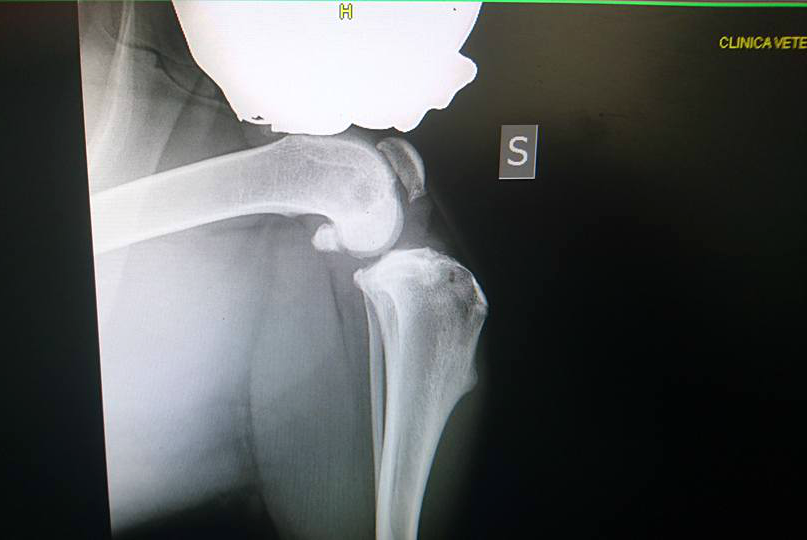

CALVATONE – Una nuova vita per lui. La seconda, in attesa di una terza che sarà al termine del tunnel in cui Capo, meticcio arrivato a ‘La cuccia e il nido’ di Calvatone, è precipitato. Una storia, la sua, come tante. Quella di chi prende un cane e poi – di fronte alle difficoltà di una convivenza – ci rinuncia. “Capo – raccontano i volontari del canile di Calvatone – è cresciuto in famiglia, e sarebbe dovuto essere così per sempre, ma qualcosa è andato storto e poche settimane fa ha fatto il suo ingresso da noi, al Canile Rifugio la Cuccia e il Nido Anpana Onlus di Calvatone. Capo è stato rinunciato dalla famiglia per presunta aggressività nei confronti della figlia. Nessun educatore, nessuno si è rimboccato le maniche, per lui c’era solo un box ad attenderlo. Capo dopo i primi giorni di disorientamento, durante i quali si disperava e tremava tutto il tempo per la paura, si è rivelato il contrario di quello che gli ex padroni avevano riferito: è un bravissimo cane dagli occhi dolci e speranzosi, con la coda perennemente in movimento per ricevere una coccola, è buono e docile con tutti i volontari e gli operatori che fin da subito l’hanno curato e amato”. Le ‘disgrazie’ però non vengono mai sole. I volontari notano in capo una difficoltà di movimento e decidono di accertarsi delle reali condizioni del meticcio ‘sorridente’. “Una persistente zoppia alle zampe posteriori, per cui sono stati effettuati alcuni accertamenti. Speravamo non fosse qualcosa di grave ma purtroppo non è stato così. Le lastre hanno evidenziato la rottura completa del crociato della zampa posteriore destra, ed il lesionamento del crociato posteriore sinistro”. Un problema, benché piuttosto serio, risolvibile. Capo va sotto ai ferri grazie alla disponibilità di Anpana a farlo curare e a quella della Clinica Sant’Eusebio di Asola disposta a venire incontro al canile con le spese – ingenti – di quel tipo di operazione. “Il 10 marzo Capo ha subito l’operazione a carico del crociato posteriore destro presso la Clinica Sant’Eusebio di Asola, e subirà un ulteriore intervento al crociato sinistro nei prossimi mesi. La prima operazione (Osteotomia piatto tibiale con lama 22,5 mm, rotazione piatto tibiale, fissazione con placca TPLO 3,5 mm 6 fori, sutura cute e sottocute e bendaggio di Robert Jones, ndr) è andata a buon fine, ora Capo dovrà restare a riposo”. Operazione, lastre e controlli sono costati 900 euro. Tutti sostenuti da Anpana. “Non potevamo non intervenire – spiega Patrizia Storti di Anpana – e così abbiamo deciso di procedere. La clinica ci ha fatto un prezzo di favore, lo staff è stato molto disponibile e di questo li ringraziamo enormemente. A favore di Capo e delle sue cure si è deciso di creare una raccolta fondi. Come ben sapete le spese qua in canile sono davvero tante, le rinunce di proprietà e gli abbandoni continuano e i cani che arrivano hanno spesso bisogno di analisi e cure mediche costose”. Per Capo – il meticcio sorridente – si è aperta una raccolta. Diverse le strade che possono consentire un aiuto al meticcio: l’adozione a distanza, il versamento di una donazione sul c/c presso la Banca CARIPARMA di San Giovanni in Croce, IBAN: IT 25 N 06230 57130 000043318875 – Causale: Donazione pro Capo, una donazione PayPal cliccando sul pulsante “fai una donazione” sulla nostra pagina facebook (questo metodo è totalmente sicuro ed affidabile, nonché facile e veloce, accetta tutte le carte di credito, anche PayPal si può utilizzare anche dall’estero), l’iniziativa “Un Uovo per Fido” con cui si possono sostenere le cure di Capo attraverso le uova solidali al cioccolato al latte o fondente che si possono trovare presso l’Ufficio del Canile Rifugio tutti i giorni dalle 14 alle 18, weekend compreso. Capo avrà una seconda possibilità in questa sua seconda vita. In attesa di una terza, magari al caldo di una casa con una famiglia dal cuore grande, disposta a prendersene cura.